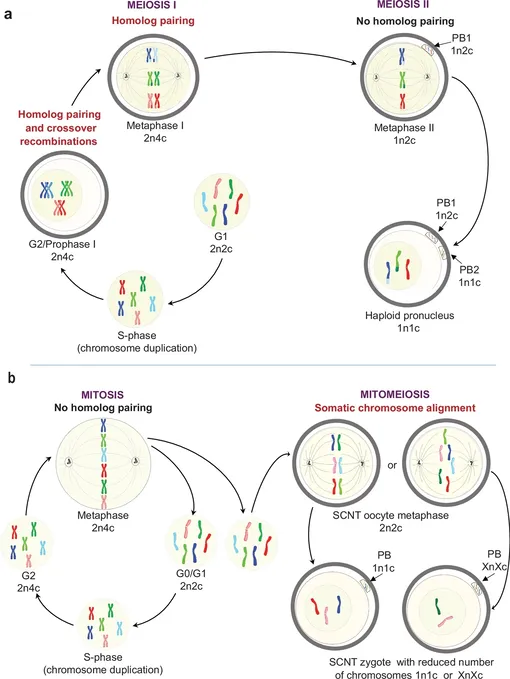

Ученые извлекали ядро из обычной клетки кожи и пересадили его в донорскую яйцеклетку, лишенную собственного ядра. Главной задачей было добиться правильного числа хромосом — половые клетки должны содержать 23 хромосомы, а не 46, как обычные клетки тела. Команда разработала метод «митомейоза», имитирующий естественное деление клетки так, чтобы один набор из 23 хромосом отбрасывался. В результате удалось создать 82 функциональные ооциты (клетки, из которых развиваются зрелые яйцеклетки).